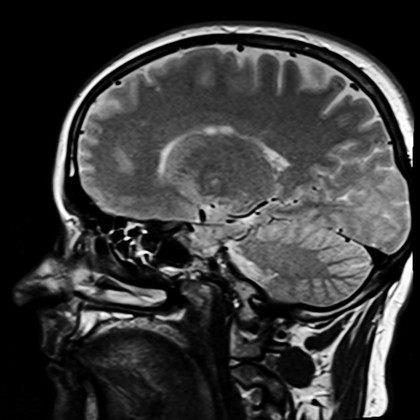

Îmbătrânirea creierului continuă să fie intens studiată, mai ales în ultimii ani, ca urmare a dezvoltării metodelor imagistice, prin care activitatea cerebrală poate fi din ce în ce mai eficient evaluată. Însă și aceste metode de investigare au limite, fapt ce poate influența interpretarea rezultatelor obținute de cercetători.

Un studiu publicat recent în jurnalul Human Brain Mapping a arătat că o astfel de situație ar fi valabilă și în cazul imageriei prin rezonanță magnetică funcțională, utilizată frecvent în investigarea îmbătrânirii cerebrale. Autorii au arătat că modificările creierului unei persoane care îmbătrânește (observate cu această metodă imagistică) ar fi de fapt determinate de schimbările vasculare, mai degrabă decât de modificările activității neuronale. O limită importantă a rezonanței magnetice funcționale este că măsoară indirect activitatea neuronală prin fluctuațiile fluxului sanguin regional. Astfel, dacă nu sunt luate în considerare și corectate diferențele de vârstă în ceea ce privește reactivitatea vasculară, acestea ar putea fi în mod greșit interpretate ca fiind modificări de natură cerebrală.

Pentru a putea vedea mai exact efectele îmbătrânirii asupra creierului, echipa de cercetători condusă de Kamen A. Tsvetanov a încercat să reducă dezavantajele rezonanței magnetice funcționale, apelând la o metodă alternativă de corecție și utilizând o combinație unică a datelor în urma scanării cerebrale în cazul a 335 de participanți cu o stare bună de sănătate, a căror activitate cerebrală a fost măsurată în timp ce se odihneau.

Cercetătorii au putut arăta astfel că diferențele care țin de vârstă și care apar pe durata realizării unor activități au de fapt o origine vasculară și nu neuronală. De aceea au propus utilizarea metodei lor de corecție în studiul îmbătrânirii creierului prin rezonanța magnetică, pentru controlul diferențelor de natură vasculară.

Echipa de cercetare a replicat studiile anterioare asupra creierului, care arătaseră o reducere a activității cerebrale în zonele vizuală și auditivă odată cu îmbătrânirea. În plus, s-au aplicat aceste corecții. Rezultatele au arătat că sănătatea vasculară ar fi cea responsabilă pentru diferențele de vârstă și nu funcționarea creierului. Cu alte cuvinte, creierul unei persoane vârstnice ar fi mult mai asemănător cu al uneia tinere decât s-a considerat până acum.

Descoperirea echipei de cercetare aduce în vedere necesitatea rafinării și îmbunătățirii rezonanței magnetice funcționale în investigarea îmbătrânirii creierului, pentru a nu pune pe seama vârstei anumite efecte care au de fapt o altă origine (de exemplu vasculară, cum am văzut deja).